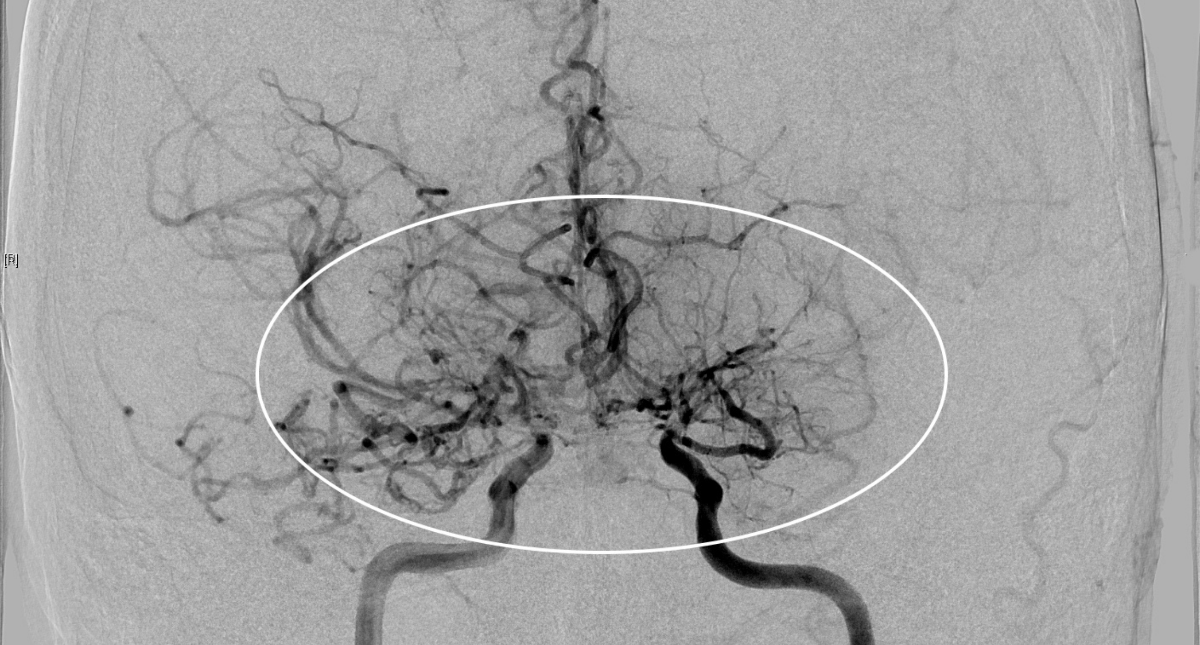

Khi nhập viện tại khoa Ngoại thần kinh, các xét nghiệm

chuyên sâu gồm MRI tưới máu não và chụp mạch số hóa xóa nền (DSA), xác định bệnh

nhân mắc Moyamoya - một bệnh lý mạch máu não hiếm gặp có tính chất tiến triển.

Các mạch máu não của bệnh nhân nhìn như “làn khói thuốc lá” trên phim chụp MRI.

nguyên nhân, bác sĩ chỉ định chụp cộng hưởng từ (MRI) sọ não. Kết quả MRI cho

thấy, hình ảnh tổn thương hẹp tắc động mạch cảnh trong hai bên và các nhánh của

đa giác Willis, xung quanh hình thành tuần hoàn bàng hệ với nhiều mạch máu nhỏ

bất thường.

Chẩn đoán hình ảnh phát hiện tình trạng hẹp hoặc tắc nghẽn

phần cuối của động mạch cảnh trong sọ, rồi lan rộng ra các động mạch não trước,

não giữa, não sau; phát hiện mạng lưới mạch máu bất thường ở vùng lân cận của

các tổn thương dạng “làn khói thuốc”. Bệnh Moyamoya nếu không được phát hiện và